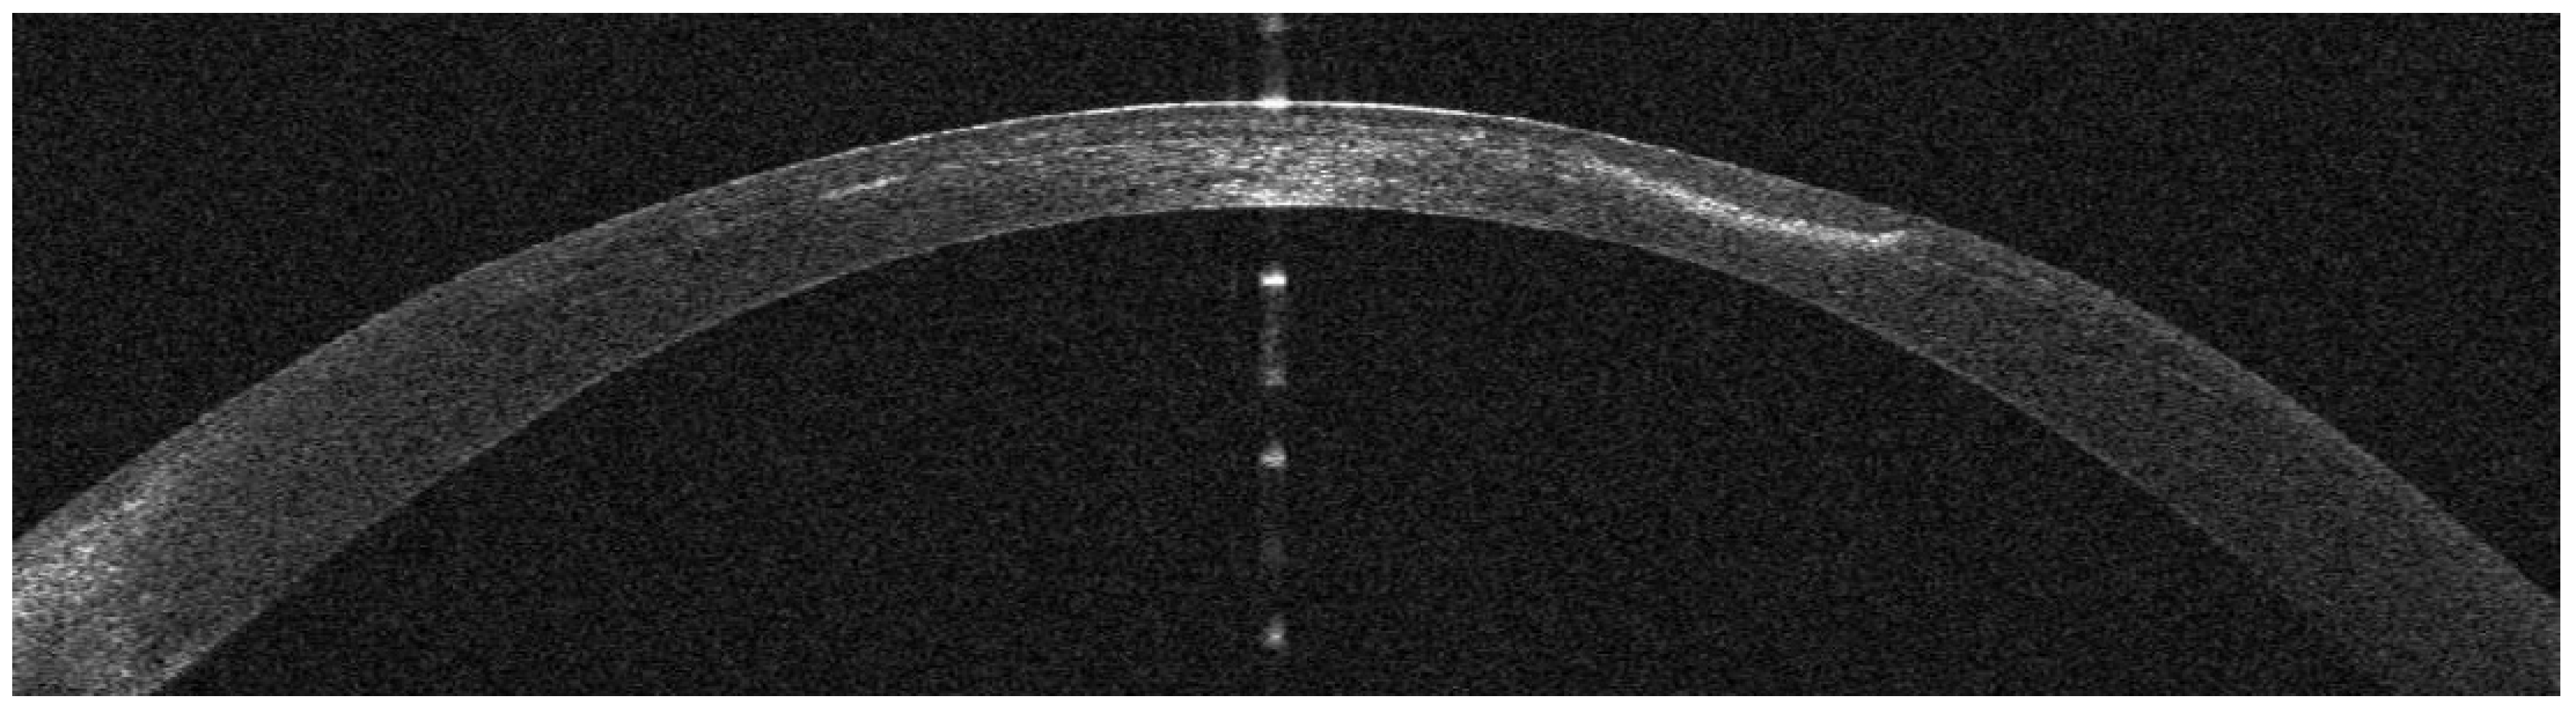

Infectious Keratitis Post-Femtosecond LASIK

AS-OCT Features